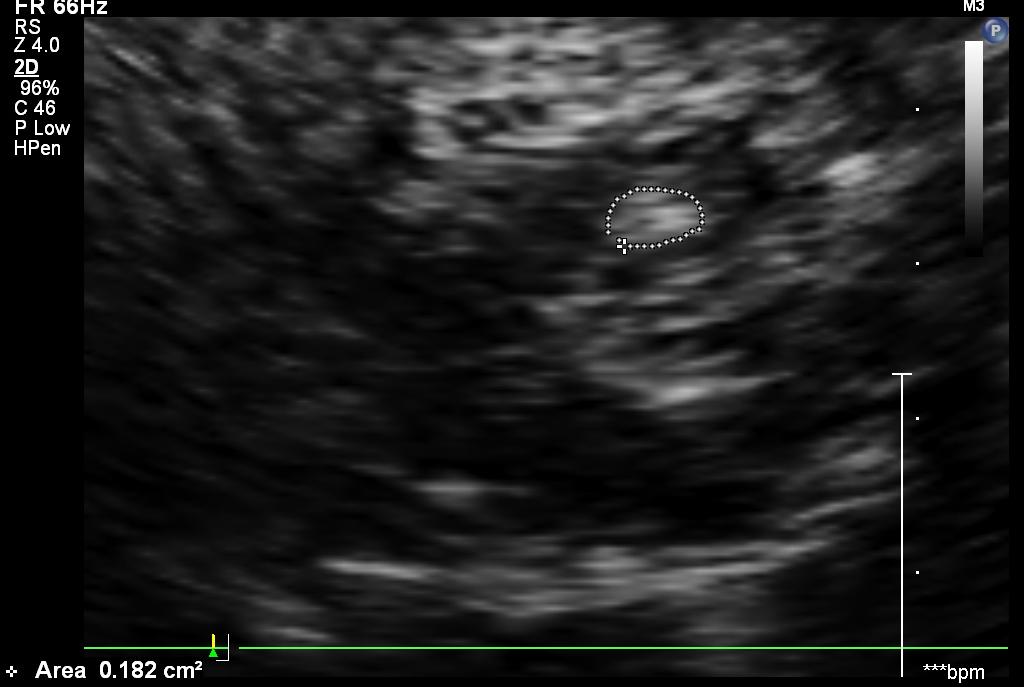

p60卓越的图像质量搭载专科探头,在妇科基础疾病的诊断,卵泡生长的

我做的b超图中葫芦形的一端里有一个椭圆形黑色的东西,请这是什么?